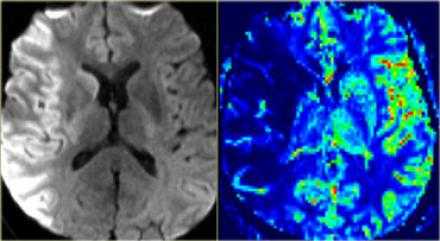

Диффузно-взвешенное изображение.

DWI наиболее чувствительна к инсульту. В результате цитотоксического отека возникает дисбаланс внеклеточной воды к Броуновскому движению, поэтому данные изменения выявляются отлично на DWI. В норме протоны воды диффундируют внеклеточно, поэтому теряется сигнал. Высокая интенсивность сигнала на DWI указывает на ограничение протонов воды диффундировать внеклеточно.

Представлены ДВИ инфаркт передней, задней, средней мозговой артерии.

Обратите внимание на изображение и предположите, где патология. После продолжите чтение. Вывод:

Есть некоторая гиподенсность и отек в левой лобной доли со старостью борозд в сравнении с контр-латеральной стороной. Далее DWI снимки того же пациента. После просмотра DWI нет сомнения, что это инфаркт. Именно поэтому DWI называют инсульт последовательностью.

Когда мы сравниваем результаты на T2WI и DWI во времени, мы заметим следующее: В острой фазе T2WI норма, но со временем зона инфаркта станет гиперинтенсивной. Гиперинтенсивность на T2WI достигает своего максимума между 7 и 30 дней. После этого сигнал начинает угасать. На DWI гиперинтенсивная область в острой фазе, а затем становится более интенсивной с максимумом на 7 дней. На DWI у пациента с инфарктом головного мозга визуализируется гиперинтенсивная область примерно на 3 недели после начала заболевания (при инфаркте спинного мозга на DWI визуализируется гиперинтенсивная область на одну неделю!). На ADC будет сигнал низкой интенсивности с минимальной интенсивностью в первые 24 часа, после сигнал будет увеличиваться в интенсивности и, наконец, становится максимально интенсивным в хроническую стадию.